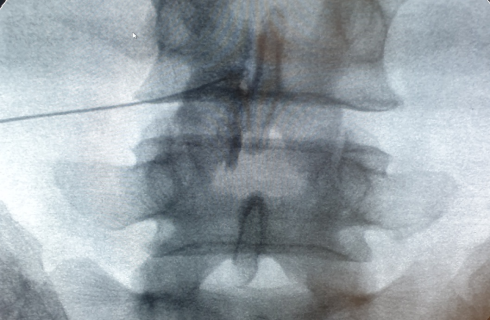

척추의 신경이 눌려 발생하는 요통과 디스크 등

척추 질환의 통증을 완화하는 가장 기본적인 시술입니다.

영상장치인 C-arm을 보며 통증의 원인이 되는 부위에

직접적으로 약물을 주입하여 압박으로 인한

염증과 부종을 제거하고, 신경을 치료합니다.